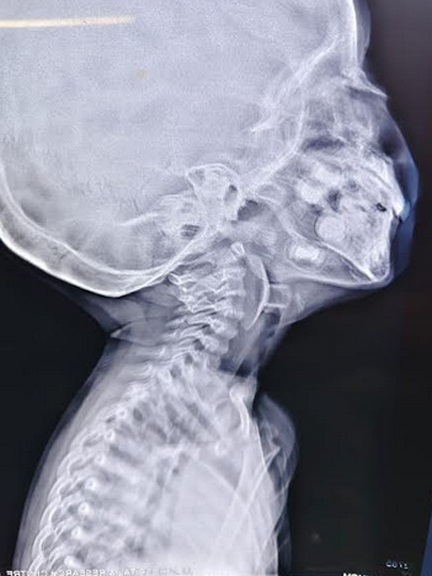

आपातकालीन विभाग में जांच के बाद पता चला कि बच्चे के श्वसन मार्ग में एक सक्शन कप एरोहेड टिप (जो आमतौर पर तीर-कमान सेट खिलौने का हिस्सा होती है) फंसी हुई थी। यह वस्तु बच्चे की जान के लिए सीधा खतरा बन चुकी थी। बिना देर किये उसे पीडियाट्रिक आईसीयू में भर्ती कर स्थिर किया गया और ईएनटी आपातकालीन ऑपरेशन थियेटर ले जाया गया।

वहाँ मुख्य चिकित्सा अधिकारी प्रभारी (चिकित्सा एवं स्वास्थ्य सेवाएं) डॉ. विनीता द्विवेदी के मार्गदर्शन में— डॉ. तनुजा और डॉ. अबानी की एनेस्थीसिया टीम ने अत्यंत नाजुक स्थिति में बच्चे के श्वसन नियंत्रण और एनेस्थेटिक प्रबंधन की जिम्मेदारी संभाली। इस बीच डॉ. अश्विन अशोक जैसवाल के नेतृत्व में (ईएनटी सर्जिकल टीम) की डॉ. प्रियंका, डॉ. रौशन और डॉ. गिरिधर के सहयोग से, डॉ. प्राची मेने के पर्यवेक्षण में बाह्य वस्तु (फॉरेन ऑब्जेक्ट) को सावधानीपूर्वक बाहर निकाला गया। कुछ ही पलों में बच्चे की सांसें सामान्य होने लगीं और माता-पिता की आँखों से राहत के आँसू बह निकले।